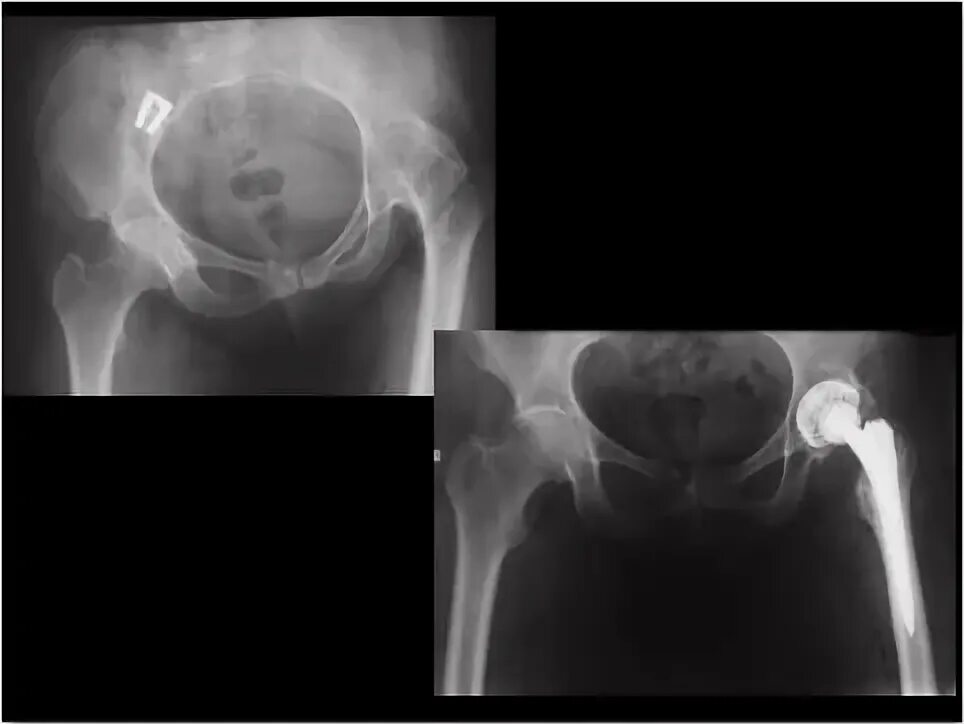

Анкилоз тазобедренного сустава